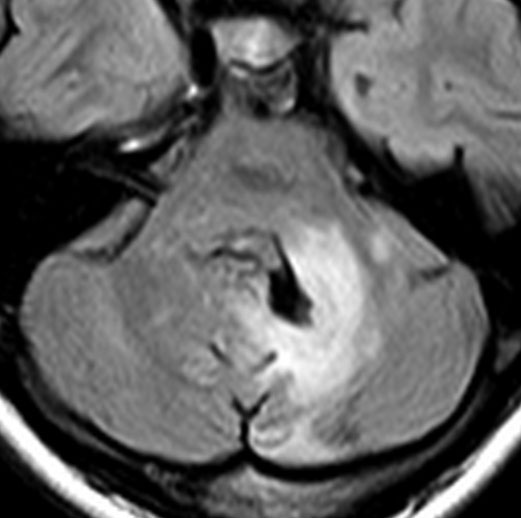

思春期の女の子にできた小脳腫瘍です。とても大きく見えますがほとんどが水たまり(のう胞といいます)。第4脳室が腫瘍で圧迫されて閉塞性水頭症になりました。のう胞の中に出血がありますが毛様細胞性星細胞腫では腫瘍内出血をしばしば見ます。右の写真で脳室が大きくなっています。こんなに大きいのに小脳症状は全くなくて,頭痛と嘔吐が症状でした。

赤で塗ったところだけが毛様細胞性星細胞腫です。これを取れば治ります。簡単な手術ですし後遺症も残りません。

手術後のMRIです。水頭症も改善してますから症状も消失しましたし,すぐに退院です o(^o^)o